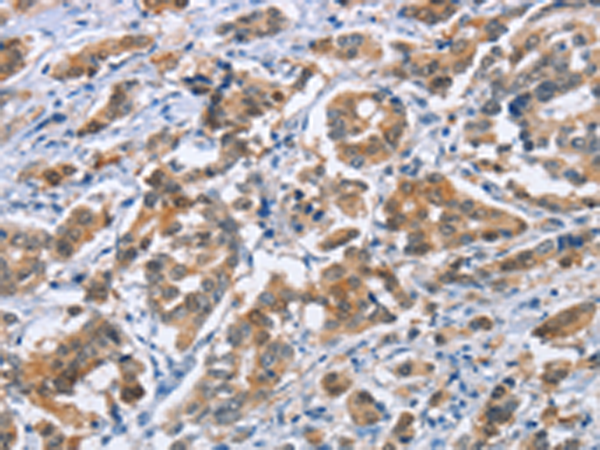

分类: 科研抗体货号: P08194别名: CPC9; CYP2C; CYP2C10; CYPIIC9; P450IIC9应用: IHC反应种属: Human